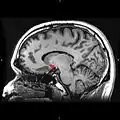

Sagittal MRI slice with highlighting (red) indicating the nucleus accumbens.

Nucleus accumbens highlighted in green on sagittal T1 MRI images